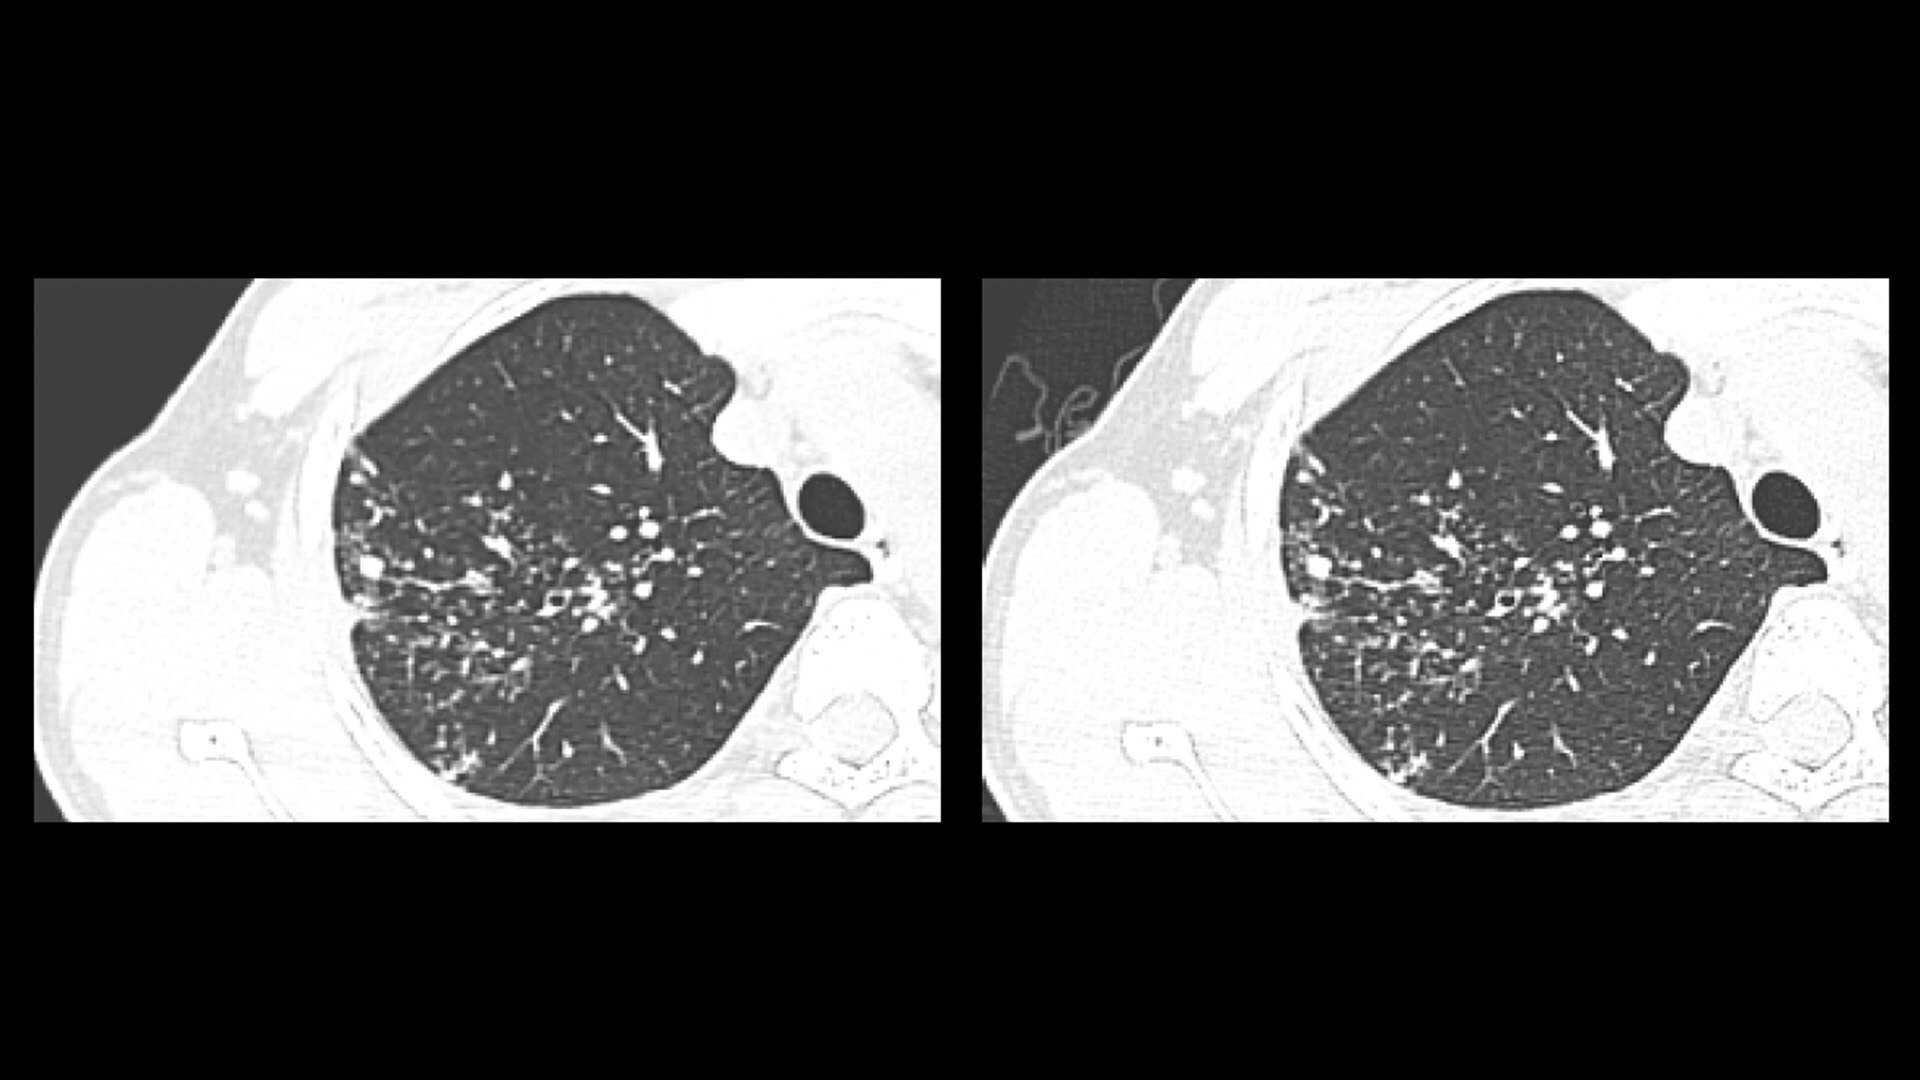

Revolutionary, deep-learning based reconstruction technology provides sharper, clearer, and accurate images

AIR™ Recon DL challenges the inherent trade-off between SNR, scan time and image resolution. Using a deep-learning based reconstruction algorithm, AIR™ Recon DL improves SNR by making use of the raw data to remove image noise and ringing. You can now produce high-quality images with shorter scan times, enabling greater patient throughput and increased return on investment.

From image noise to ringing, AIR™ Recon DL uses deep learning to prevent artifacts from ever being introduced to your images. The result is TrueFidelity™ MR Images.